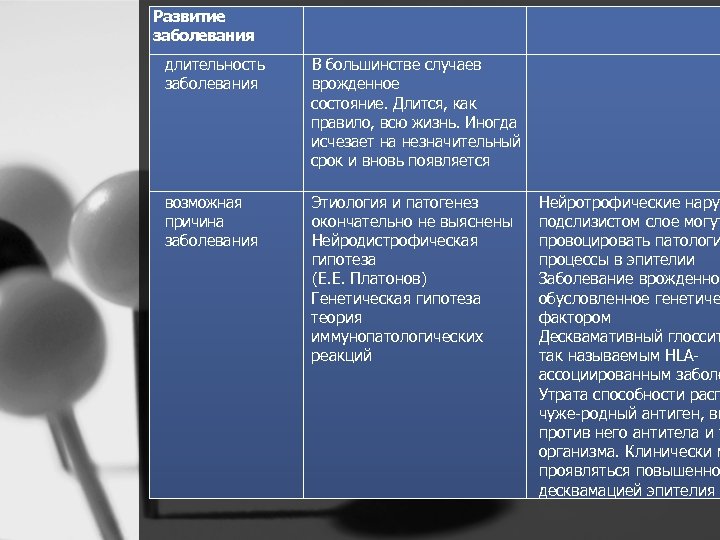

Анамнез пол возраст Чаще у женщин Преимущественно в детском воз расте, но нередко выявляется и у взрослых перенесенны Заболевания желудочно е кишечного тракта и Экссудативный диатез у сопутствующи детей е Эндокринные нарушения, заболевания острые инфекционные заболевания, коллагенозы, заболевания кроветворной и нервной систем Гиповитаминозы Вь В 3, В 5 Складчатый язык Нарушается усвоение витаминов, обеспечивающих нормальную реген метаболизм клеток эпителия. Повы чувствительность слизистой об рта к раздражителям. Возможно, аллергический фактор при экссудат диатезе. Снижают резистентность с оболочки рта. Прием лекарственны препаратов для лечения этих забол ведет к сенсибилизации организма вызывать патологические изменени слизистой оболочки языка. Нейрот нарушения в подслизистом слое мо провоцировать повышенную десква эпителия языка Нарушение обменных и окислитель восстановительных процессов Десквамативный глоссит примерно случаев сочетается со складчатым я

Развитие заболевания длительность заболевания В большинстве случаев врожденное состояние. Длится, как правило, всю жизнь. Иногда исчезает на незначительный срок и вновь появляется возможная причина заболевания Этиология и патогенез окончательно не выяснены Нейродистрофическая гипотеза (Е. Е. Платонов) Генетическая гипотеза теория иммунопатологических реакций Нейротрофические наруш подслизистом слое могут провоцировать патологи процессы в эпителии Заболевание врожденно обусловленное генетиче фактором Десквамативный глоссит так называемым HLA ассоциированным заболе Утрата способности расп чуже родный антиген, вы против него антитела и у организма. Клинически м проявляться повышенно десквамацией эпителия